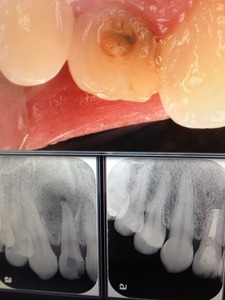

では、細菌がすでに根の先まで進攻し、病変が骨に出来ている時は?

つまり消毒のクスリを置いて、次回に詰めるか?どうかです。

実験的には、クスリを置いた方が細菌数が減り、結果も良くなるハズなのですが?

統計的には、一回でも複数回でも治り具合に差は出ませんでした。